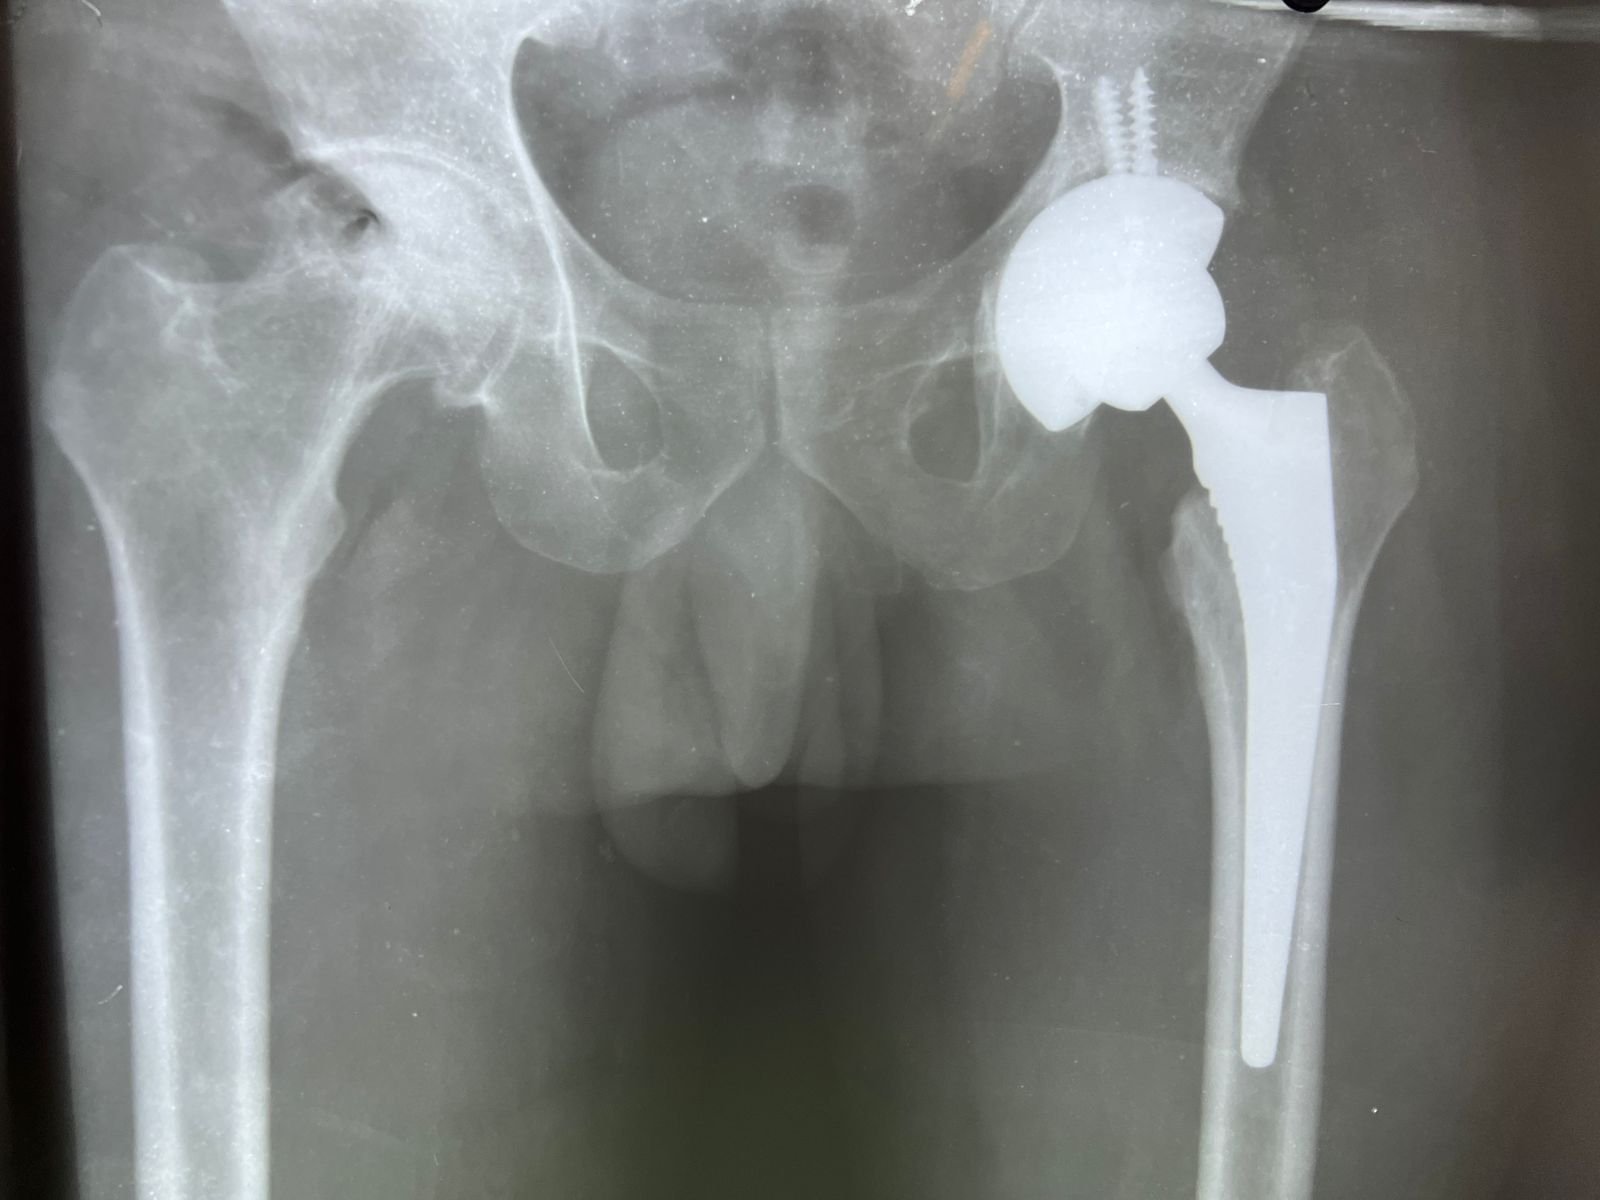

plaster & operation | Total Hip replacement case |